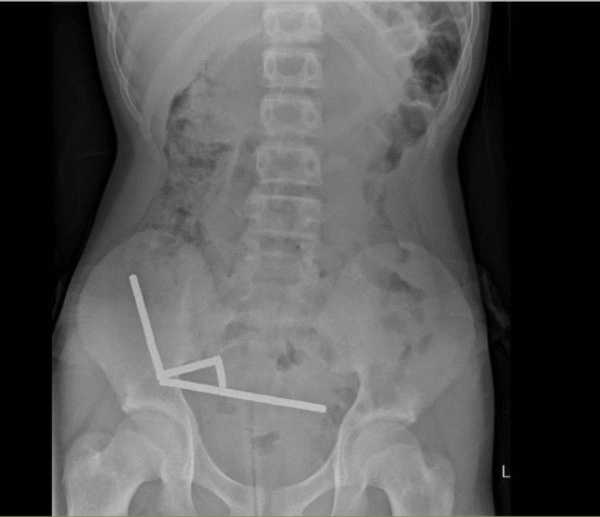

Підліток звернувся до лікарів зі каргами на сильний біль у животі. Він зізнався, що кілька днів тому міг проковтнути близько сотні маленьких магнітних кульок. Під час обстеження медики виявили в його кишківнику чотири магнітні ланцюги, які притягувалися одне до одного, стискаючи тканини та викликаючи некроз.

Хірургам довлелося провести операцію та видалити пошкоджені ділянки кишечника. Після втручання хлопчик швидко одужав і за вісім днів повернувся додому.